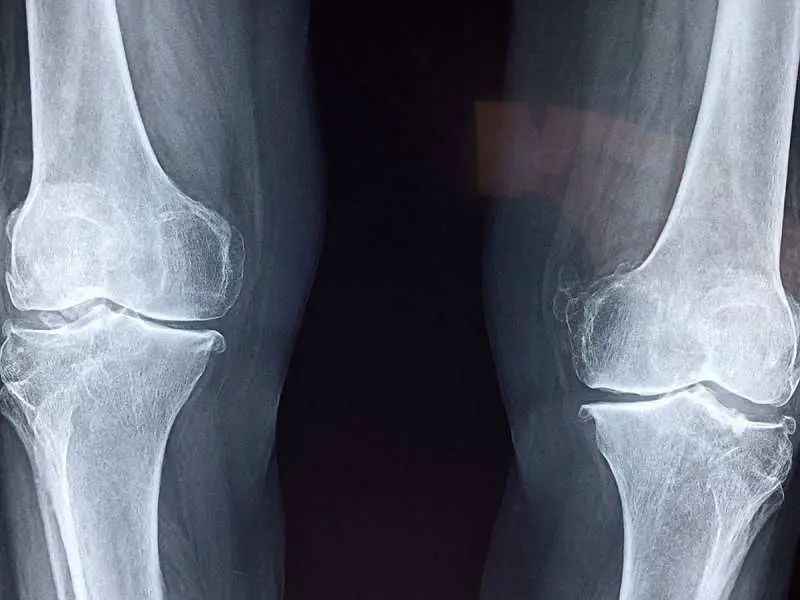

दक्षिण कोरिया के वैज्ञानिकों ने हड्डियों के इलाज को आसान बनाने वाली एक अनोखी तकनीक खोज निकाली है। सॉन्गक्यूंकवान यूनिवर्सिटी के रिसर्चर्स ने आमतौर पर इस्तेमाल होने वाली ग्लू गन को इस तरह बदला कि वह टूटी हुई हड्डियों पर सीधा हड्डी जैसा पदार्थ प्रिंट कर सके। अब तक यह तकनीक जानवरों पर आजमाई गई है और प्रयोग पूरी तरह सफल रहा है।